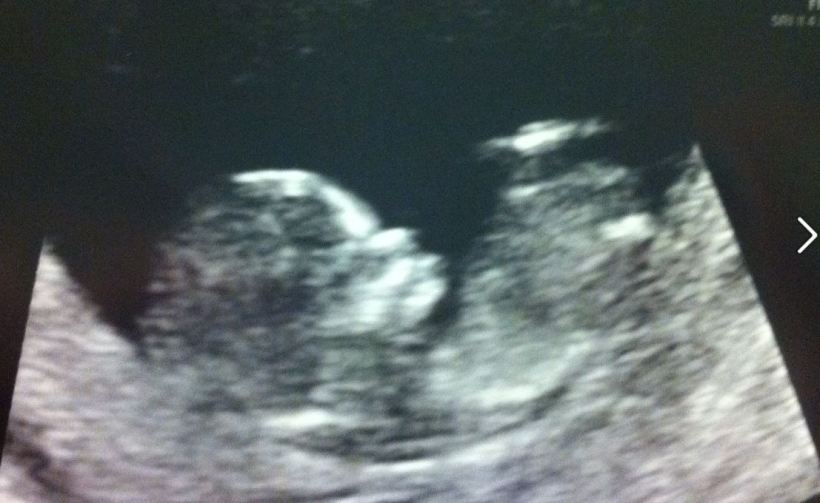

This post is about the fact that while I am 14 weeks pregnant and very happy to be so, I am still worried about things that can go wrong. I have seen the picture ^^^ Hi baby! and I definitely feel tired and there are some cravings (peanut butter and a constant need for milk) but other than that, there aren’t yet visible signs of my being with child. Several people I have told that I am pregnant were far more excited than I was and I couldn’t put my finger on why. By the way, I don’t think that there is anything wrong with any level of excitement, as it is MY pregnancy and how I FEEL will be how I FEEL and feelings are not bad or good, they just are. That took me almost 25 years to learn but it’s a very important thing to remember.